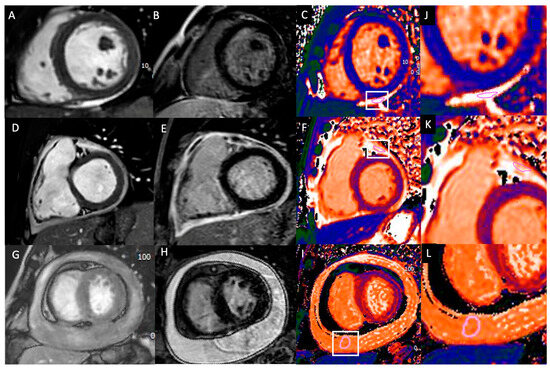

3.2. CMR Features in Acute Pericarditis Patients

| Pericardial T1 mapping, ms | 2137 ± 519 | 3268 ± 362 | 0.001 |